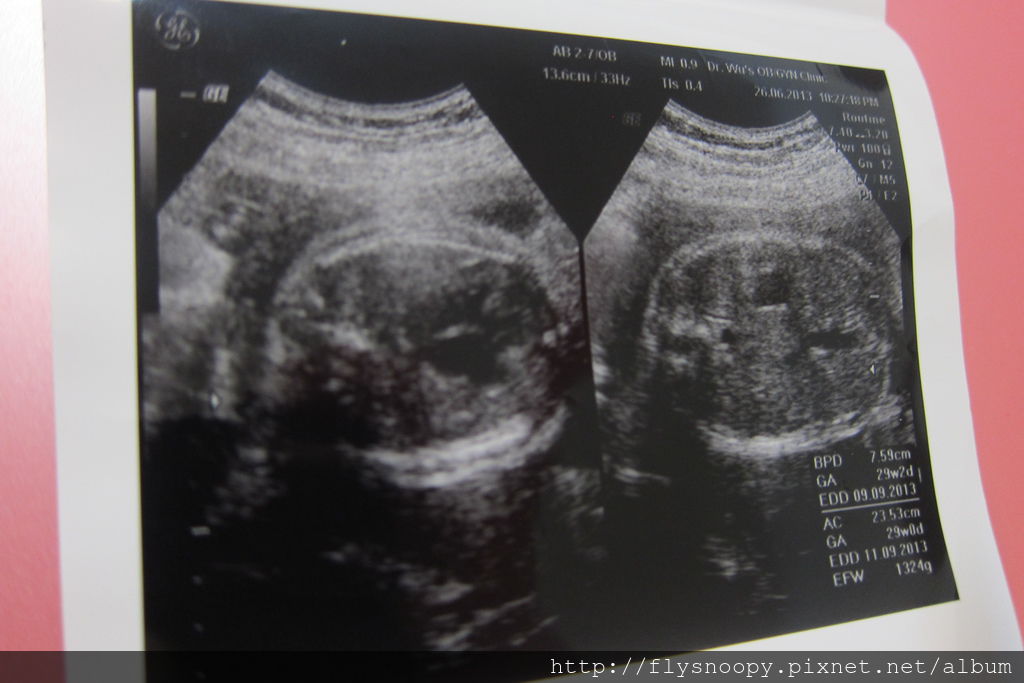

第6次產檢記錄

體重:62.6

血壓:102/57

尿糖、尿蛋白:正常

EFW:1324g

這次照音波時又沒有臍帶繞頸了,希望樂樂的情形可以一直這麼穩定